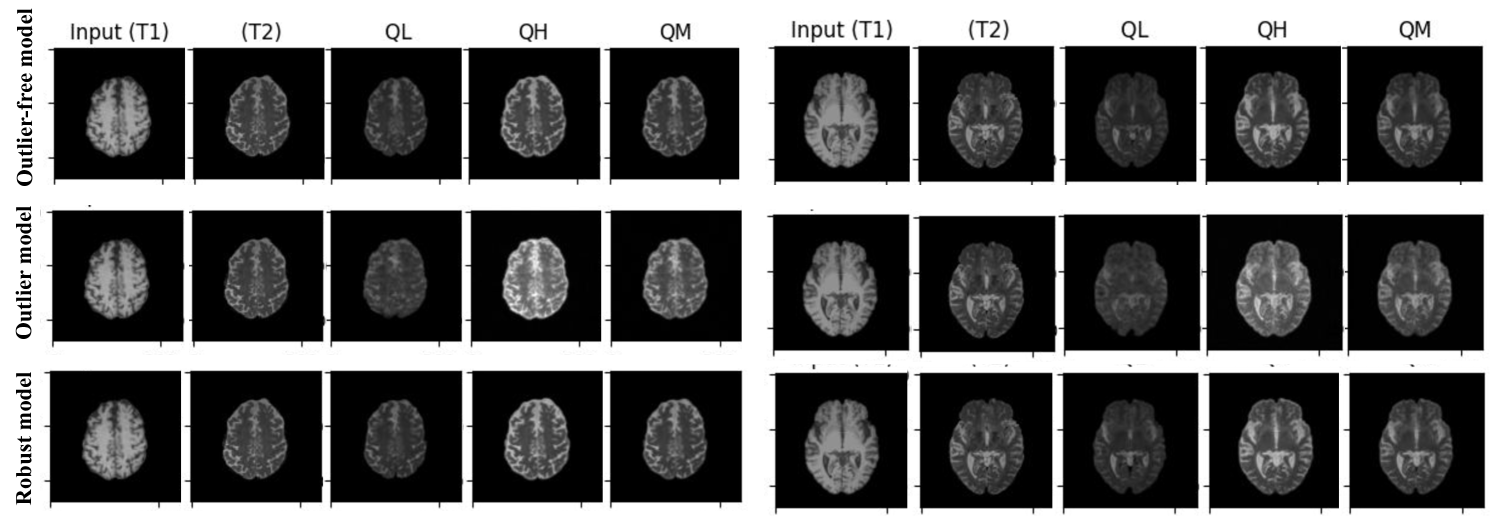

Fig. 3: Estimating T2 MRI QL(0.05),QH(0.95),QM(0.5) for diffusion models from T1 MRI. Comparing the estimated quantiles using the non-robust and robust (β𝛽\beta-QR) model with the outlier free model.

3.3 Quantile regression for uncertainty estimation in diffusion models

In this section, we present an experiment aimed at showcasing the effectiveness of our proposed robust quantile regression approach in a medical imaging task. Specifically, we focus on addressing the outlier problem in an image translation task, where we employ a diffusion model to predict various quantiles of T2-weighted brain MRI images based on input T1-weighted images.

Our training dataset consists of two distinct groups of subjects: (i) Lesion-free subjects that come from the Cam-CAN dataset (in-liers) [21], representing individuals without any brain lesions, and (ii) Lesion subjects that are sourced from the BRATS dataset [22] who do have brain lesions, thereby introducing outliers into the dataset. Training the diffusion model solely on the Cam-CAN data and using the loss function in (1) yields a reliable model that successfully captures the relationship between T1 and the quantiles of T2 images. However, introducing the “outlier” lesioned brain images from the BRATS dataset into the training set and using the same loss function significantly perturbs the training process, resulting in a notably less reliable model and corrupted quantiles. To mitigate the adverse effects of the outlier samples and restore model reliability, we integrate the proposed robust loss function presented in (4) into the training process. This loss function is designed to down-weight the influence of outliers during training, effectively bringing the model’s performance closer to that of the model trained solely on clean data from the Cam-CAN dataset. The robust loss function was employed to train the model with the combined Cam-CAN and BRATS data sets. The results of this experiment are illustrated in Fig. 3, providing a qualitative comparison of the trained models. Table 2 shows our quantitative results. These results unequivocally demonstrate that the inclusion of the robust loss function during model training significantly enhances the model’s robustness to outliers, resulting in a reliable model that closely approximates the performance of the model trained exclusively on clean data. We estimated 0.05,0.5 and 0.95 for this dataset. For comparison of the robust and non-robust models, we calculated: (1) the MSE between the estimated quantiles and the outlier-free model predicted quantiles; and (2) the MSE between the predicted median and the ground-truth T2 image. We tuned the β𝛽\beta parameter using a validation set.